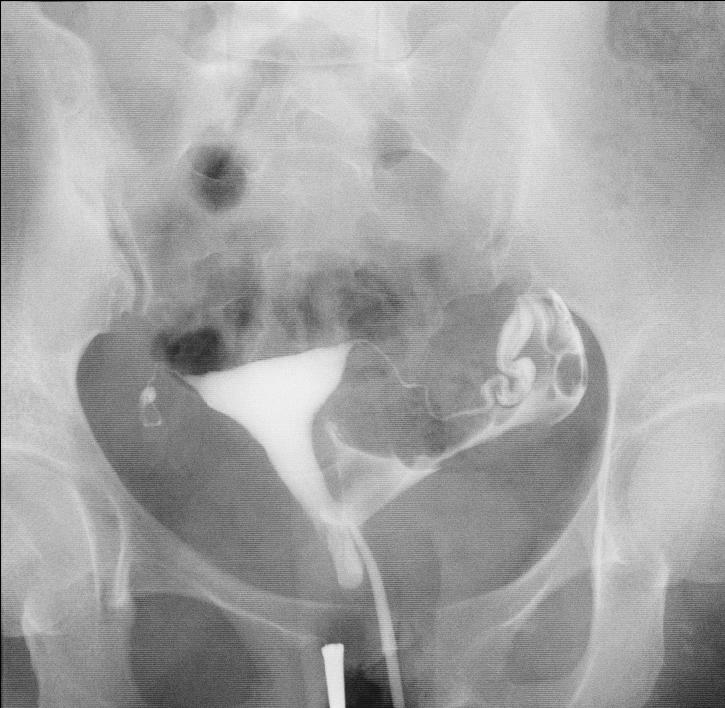

2019年2月27日,由于基层大夫跟我关系很好,把她介绍到我这里看看,来时就说“能看就看,如果花费太大,就不看了”,我就先让她做了一个无痛不插管子宫输卵管造影检查,结果显示:左侧输卵管通而不畅,右侧输卵管不通,通过片子,我觉得她的右侧输卵管已经没有希望,来的太晚了,剩下的左侧输卵管还不是完全通畅的,目前的情况是想花钱少又想怀孕,就好好听话,好好治疗,不然宫外孕就更惨了。